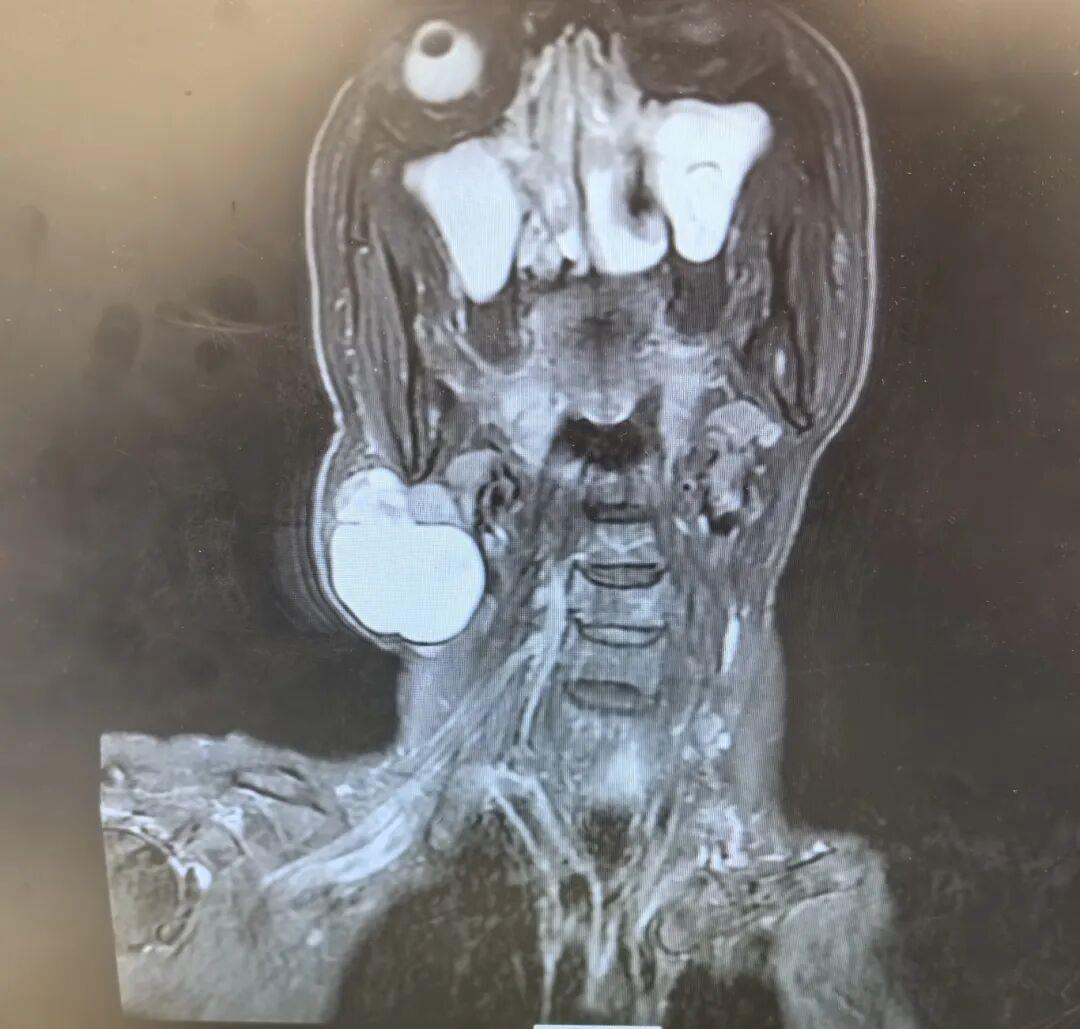

71 岁的韩女士右侧颈部曾有一处 0.5cm0.5cm 的包块,十年间无明显变化,本未引起过多关注。然而1年前,这颗 “安静” 的肿物毫无征兆地快速生长,最终增大至 8.0cm8.0cm,给韩女士的生活带来严重困扰,随即前往西安市红会医院耳鼻咽喉头颈整形修复科就诊。门诊接诊的李莹医生详…